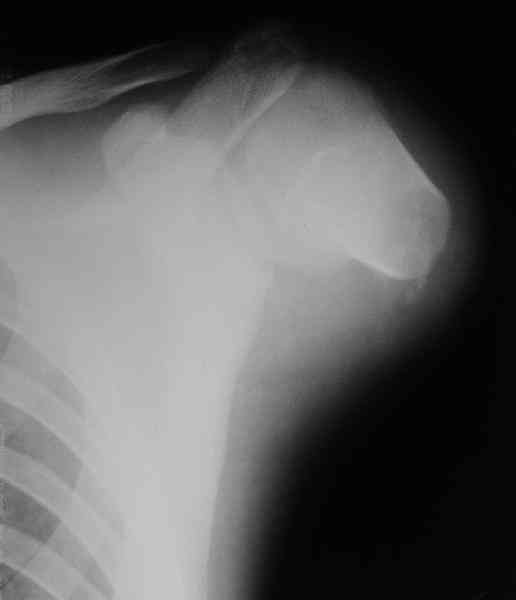

Здравствуйте, коллеги. Просьба помочь пациенту 17 лет.

Травма паровозная 4-го марта, формирование культи плеча в больнице по месту жительства.

Есть ли у кого-нибудь возможность выполнить протезирование современными технологиями и где это можно сделать, в том числе за рубежом?

К сожалению, даже за рубежом при такой короткой культе трудно делать протез. Можно посоветовать дистракционное удлинение для большего удобства адапторования протеза.

А где-нибудь это возможно сделать в одном месте или удлинение сделать лучше у нас, на какую величину?

In this complicated case I would either try to elongate or try a myosensitive computerised prosthesis - They are rare and used mostly for kids.